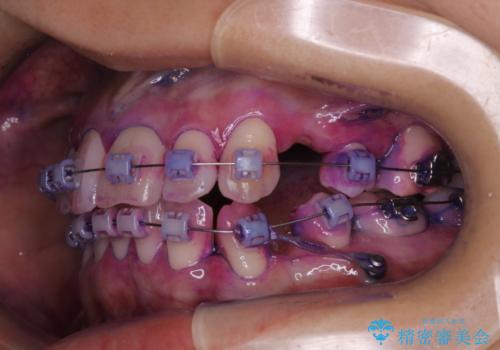

- ワイヤー矯正中に、口臭や汚れが気になり綺麗にクリーニングしたいとのことでした。染め出しをしての歯磨き指導とPMTC60分コースを行いました。

ワイヤー矯正中はブラッシングが難しくなるため、磨き残しが多くなることがあります。

ご自身でのブラッシングケアでは、歯周ポケットの中に歯ブラシの毛先が届くのはわずか2ミリ程です。軽度の歯周炎の場合でも歯周ポケットは3ミリほどあります。歯茎の中に長く汚れが溜まると、歯石や細菌などがつき、口臭の原因にもなります。

適切な道具を使って、適切なブラッシング方法を習得することで、磨き残しを減らすことができます。

また、矯正で歯の移動があると今までなかったところに隙間が出てきたり、ガタつきが解消されてきたりすることで、お口の中の環境が変わります。

矯正治療中も清潔な口腔内を保つことは、とても大切です。そのため、定期的に専門的な機械・材料を使用したProfessinnalcleaning(pmtc)を行うことがおススメです。